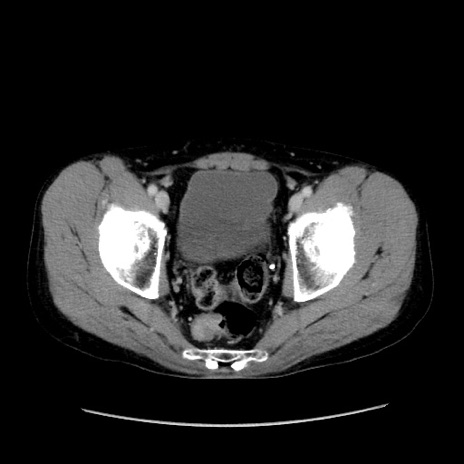

冠状断像

【症例】40歳代 男性

【主訴】腹痛

【現病歴】4時間ほど前に電車に乗車中に臍部上より腹痛出現。徐々に増悪し起立困難となり、救急外来受診。生ものは数日食べていない。今朝お雑煮を食べた。

【身体所見】BT 36.8℃、BP 117/84mmHg、HR 91/min、SpO2 97%、苦悶様、腹部:臍上部広範囲圧痛あり、反跳痛±

【データ】WBC 8100、CRP 0.03